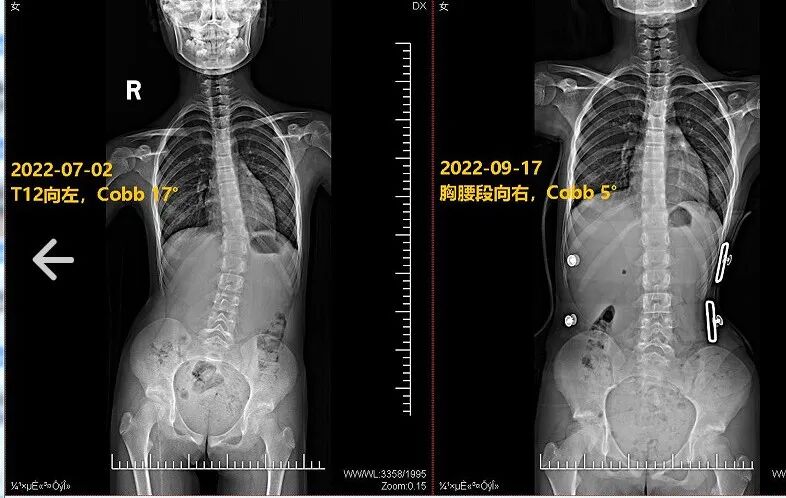

图为项目训练前和训练后对比照